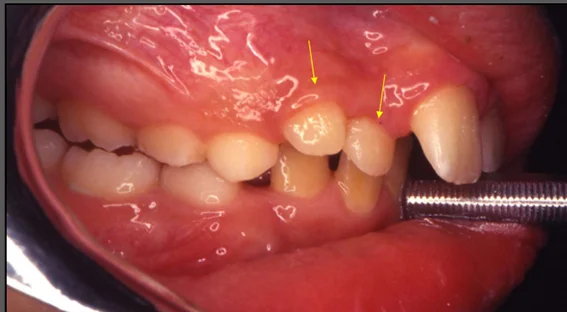

• Quando há agenesia de um dente de um lado, normalmente o dente simétrico do outro lado costuma apresentar variações de forma, como por exemplo ser mais pequeno ( ver imagem);

• Os terceiros molares e os incisivos laterais superiores, são os que mais sofrem de agenesias dentárias